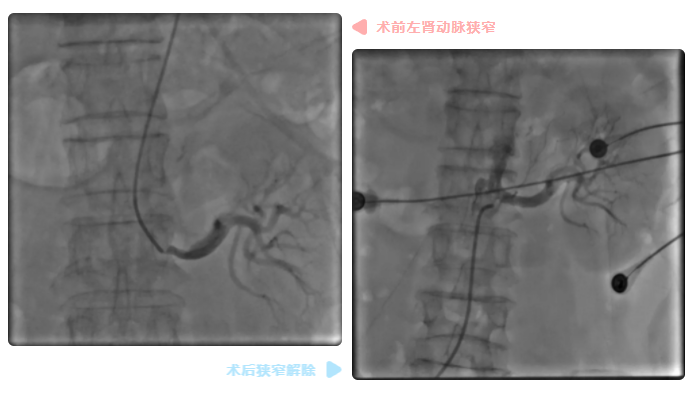

与此同时,徐先增主任还发现,岑大爷的右肾动脉完全闭塞,左肾动脉也存在严重狭窄。这意味着,患者随时可能发生猝死、心力衰竭、高血压难以控制、肾功能恶化等致命状况。

先处理左肾动脉严重狭窄。左肾动脉主要考验的是眼力和手上功夫。眼疾、手稳,手随眼动、手眼协调,脑袋时刻警醒,支架精准定位,第一枚支架成功植入左肾动脉近段,狭窄完美解除。